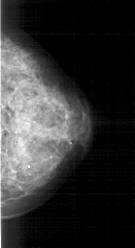

A_1283_1.LEFT_MLO

LEFT_MLO LINES 5086 PIXELS_PER_LINE 1861 BITS_PER_PIXEL 12 RESOLUTION 43.5 OVERLAY